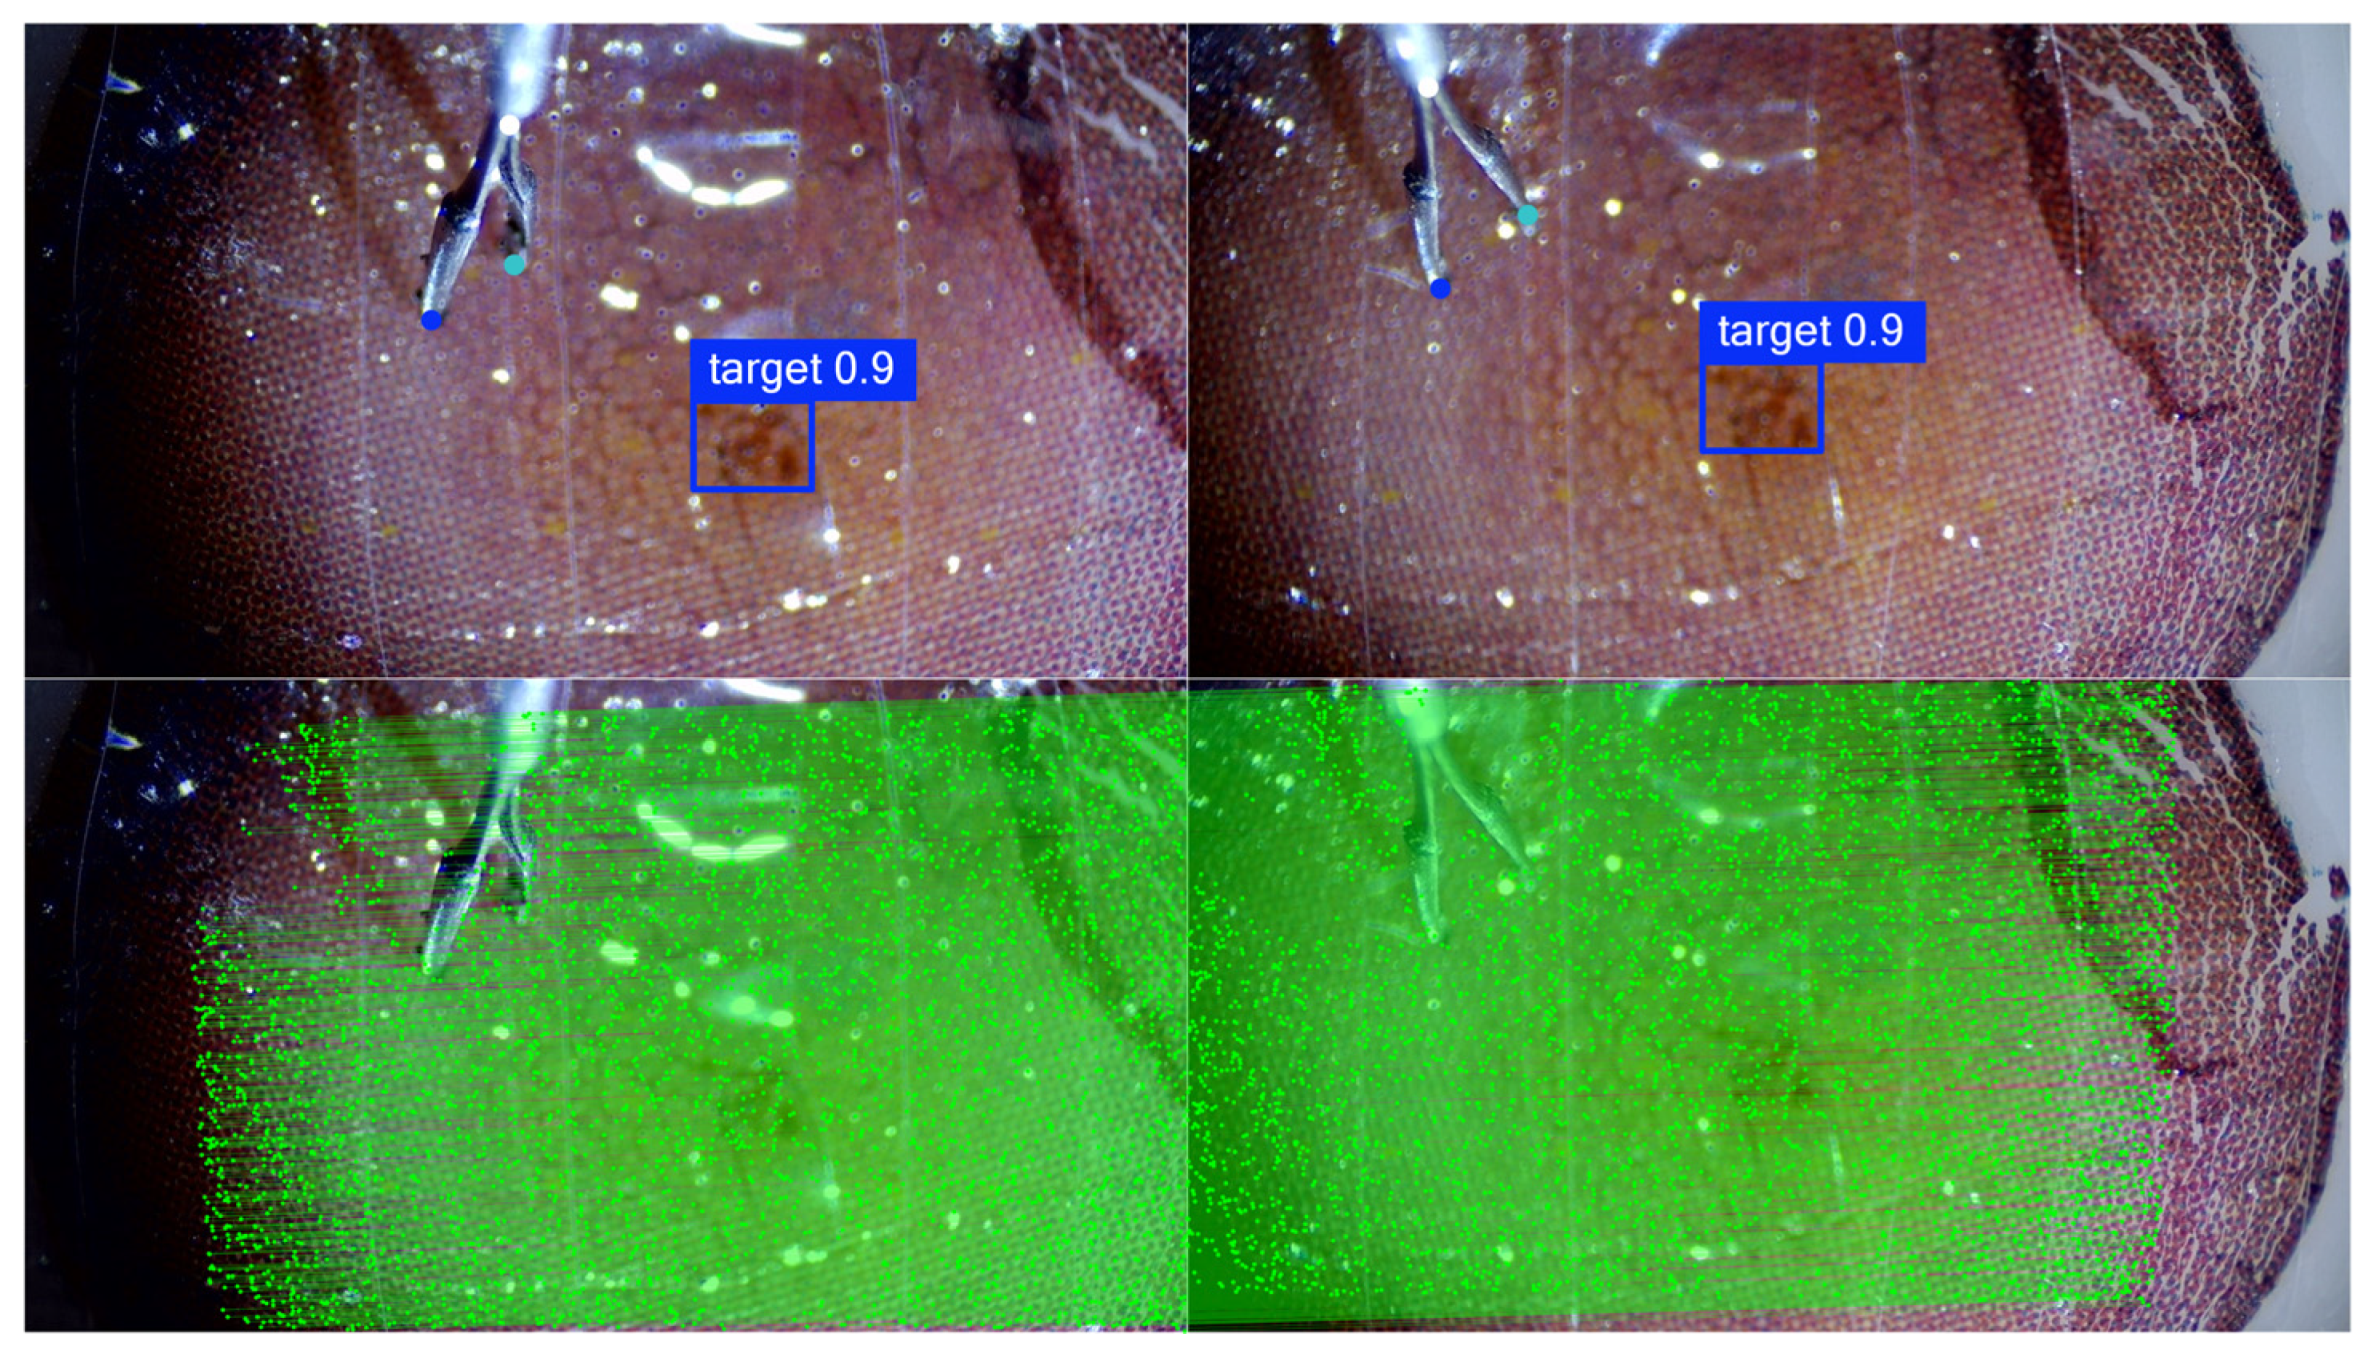

2.3. Surgical Scene Perception Method Based on Multivision Tasks

4.2. Surgical Scene Perception Network Training